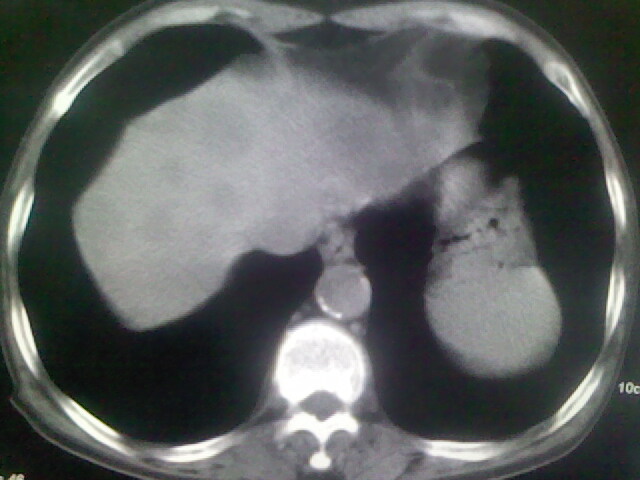

男,70y,胃占位,重度贫血,黑便3月余,伴恶心,纳差,乏力

肝内弥漫低密度---转移瘤

右上肺周围型肺癌,肝内多发低密度影---转移瘤?建议增强;胃壁明显增厚.

右上肺周围型肺癌,肝内多发低密度影---转移瘤.

1)考虑右肺上叶周围型肺癌并纵隔及右颈部淋巴结转移,肝脏多发性转移。2)肺气肿。3)冠状动脉及主动脉钙化。

1、右肺上叶周围型肺癌并纵隔、颈部淋巴结转移,肝多发转移灶。

2、胃充盈欠佳,不能确定。